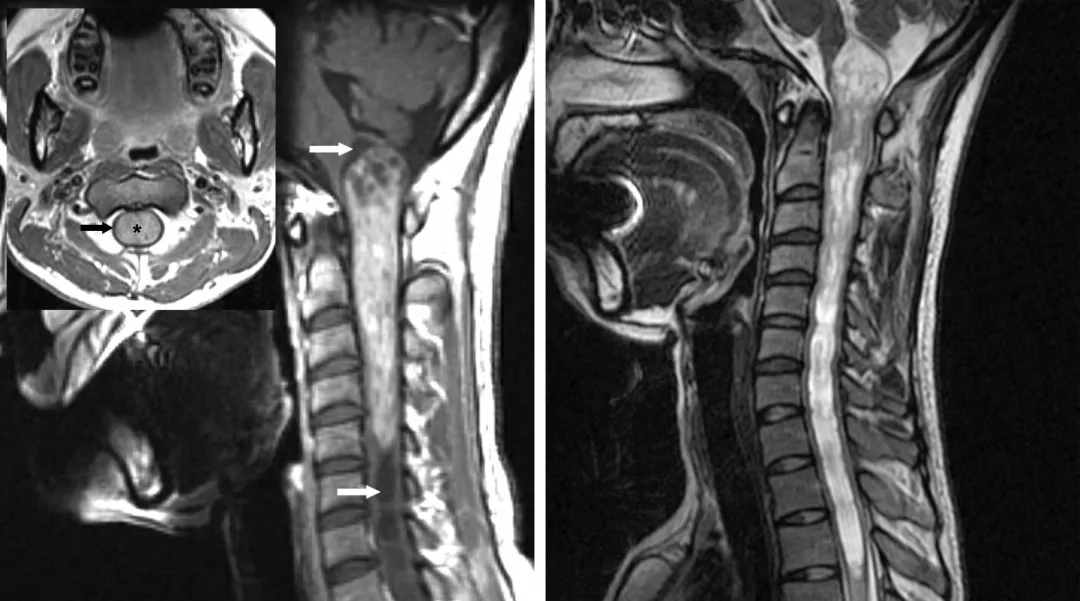

图1:所示颈髓室管膜瘤典型影像学表现:不均匀强化,肿瘤上下极脊髓空洞(白色箭头),呈对称性膨胀性生长,正常脊髓被挤压变薄(黑色箭头,左图).注意髓内空洞两端的T2相高信号(右图)

图2:颈段室管膜瘤伴有少量强化,肿瘤下极可见一小出血灶(箭头所示,右图)。